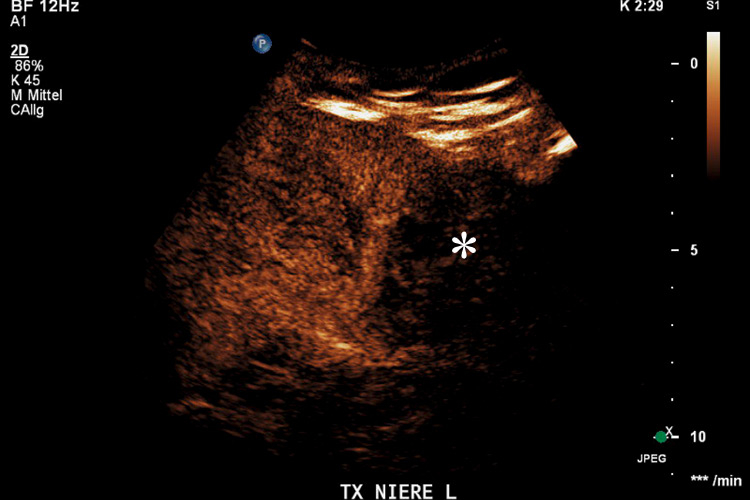

Figure 3

Transplanted kidney with hypoechoic region at the lower pole (*) on B-mode ultrasound (A). Corresponding CEUS imaging with devascularised region at the lower pole (*) in the transplanted kidney (B).

Furthermore, the use of CEUS has emerged as an excellent tool for assessing vascular complications of renal transplants by imaging the microcirculation similarly to that of the native kidney [39]. The sensitivity in the detection of transplant infarction is also very high (fig. 3). Due to the ability to image flow in the microcirculation, the infarcted size on CEUS may appear even smaller than on the corresponding colour Doppler ultrasound. Also cortical necrosis in renal transplants can be clearly depicted and is rendered more conspicuous by CEUS which allows a better immediate clinical management.